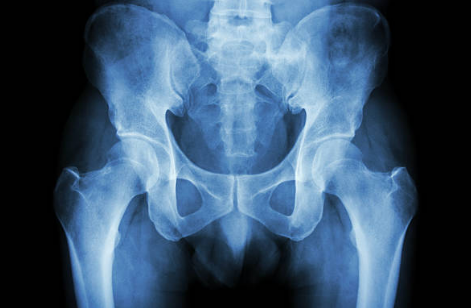

고관절 통증은 다양한 원인으로 인해 발생할 수 있으며, 일상생활에 큰 불편을 초래할 수 있습니다. 이 통증은 나이와 상관없이 누구에게나 발생할 수 있지만, 특히 고령층에서 자주 나타나며, 증상은 앉거나 서 있을 때의 통증, 걸음걸이의 변화, 운동 범위의 제한 등으로 다양합니다. 이러한 통증은 고관절의 구조적인 문제나 외상, 염증 등 여러 원인에 의해 유발될 수 있으며, 심한 경우 수술이 필요할 수도 있습니다.

고관절 통증은 다양한 원인으로 발생할 수 있으며, 여러 증상이 나타날 수 있습니다.